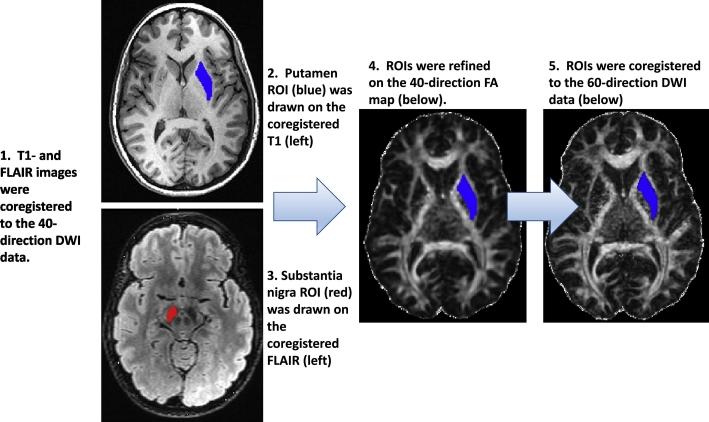

The cardinal movement abnormalities of Parkinson's disease (PD), including tremor, muscle rigidity, and reduced speed and frequency of movements, are caused by degeneration of dopaminergic neurons in the substantia nigra that project to the putamen, compromising information flow through frontal-subcortical circuits. Typically, the nigrostriatal pathway is more severely affected on the side of the brain opposite (contralateral) to the side of the body that manifests initial symptoms. Several studies have suggested that PD is also associated with changes in white matter microstructural integrity. The goal of the present study was to further develop methods for measuring striatonigral connectivity differences between PD patients and age-matched controls using diffusion weighted magnetic resonance imaging (MRI). In this cross-sectional study, 40 PD patients and 44 controls underwent diffusion weighted imaging (DWI) using a 40-direction MRI sequence as well as an optimized 60-direction sequence with overlapping slices. Regions of interest (ROIs) encompassing the putamen and substantia nigra were hand drawn in the space of the 40-direction data using high-contrast structural images and then coregistered to the 60-direction data. Probabilistic tractography was performed in the native space of each dataset by seeding the putamen ROI with an ipsilateral substantia nigra classification target. The effect of disease group (PD versus control) on mean putamen-SN connection probability and streamline density were then analyzed using generalized linear models controlling for age, gender, education, as well as seed and target region characteristics. Mean putamen-SN streamline density was lower in PD on both sides of the brain and in both 40- and 60-direction data. The optimized sequence provided a greater separation between PD and control means; however, individual values overlapped between groups. The 60-direction data also yielded mean connection probability values either trending (ipsilateral) or significantly (contralateral) lower in the PD group. There were minor between-group differences in average diffusion measures within the substantia nigra ROIs that did not affect the results of the GLM analyses when included as covariates. Based on these results, we conclude that mean striatonigral structural connectivity differs between PD and control groups and that use of an optimized 60-direction DWI sequence with overlapping slices increases the sensitivity of the technique to putative disease-related differences. However, overlap in individual values between disease groups limits its use as a classifier.